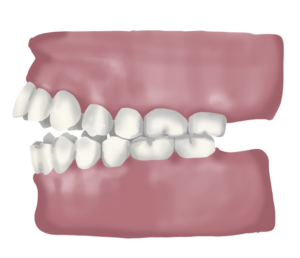

Classe II Molar

La classe II molar es dona quan la mandíbula està excessivament retruïda respecte el maxil·lar. Avaluem els mil·límetres de retrusió agafant com a referència la posició dels primers molars definitius .

Una mandíbula excessivament retruïda pot provocar problemes funcionals ja que tindrem una compressió dels teixits tous de l’articulació temporo mandibular i també tindrem una excessiva tensió a nivell muscular ja que no és una posició còmoda per mastegar i exigeix un esforç extra al cos. Sovint trobem també una sèrie d’alteracions posturals associades, el que anomenem síndrome de disfunció postural descendent, en el qual es poden invertir les curvatures vertebrals en els casos més accentuats.

A part d’aquest problema funcional, la classe II també sol suposar un problema estètic per l’individuja que les dents inferiors queden molt en segon pla i el mentó molt enrere respecte les dents de dalt.